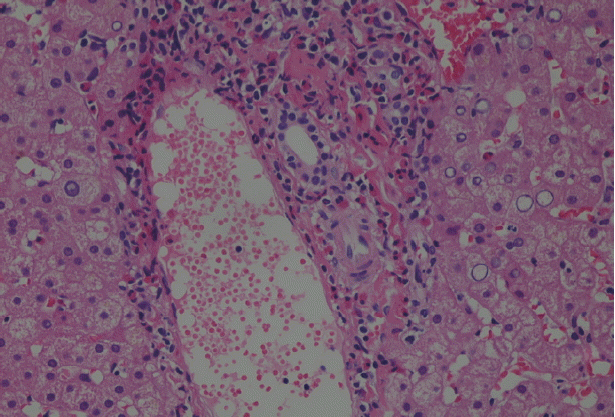

Because malignancy was initially considered, laparoscopic liver biopsy under visual control was performed at the Department of surgery on 23 June 2016. The liver biopsy was then obtained which showed liver tissue with eosinophil accumulation around the hepatobiliary system. Moreover, a detailed re-evaluation of liver biopsy in National Institute of Parasitic Diseases, Chinese Center for Disease Control and Prevention (NIPD) (15 August 2016) revealed histopathological features suggesting a parasitic infection (Fig. 2).

Pathological section: a small portion of the obtained material comprised hepatocytes, while the rest was made of young granulation tissue infiltrated by eosinophils and other inflammatory cells. Portal fields were normal in size, mild to moderately infiltrated, mainly by eosinophils, with small amounts of other inflammatory cells. Glycogenated nuclei were observed in the parenchyma. Inflammatory cells of the same types found in portal fields were observed in the sinusoids (HE stain, ×200).

Fig. 2 Pathological section: a small portion of the obtained material comprised hepatocytes, while the rest was made of young granulation tissue infiltrated by eosinophils and other inflammatory cells. Portal fields were normal in size, mild to moderately infiltrated, mainly by eosinophils, with small amounts of other inflammatory cells. Glycogenated nuclei were observed in the parenchyma. Inflammatory cells of the same types found in portal fields were observed in the sinusoids (HE stain, ×200).